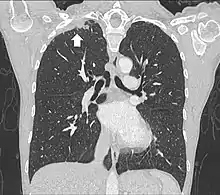

Le scanner thoracique permet d'analyser avec précision la localisation de la tumeur, de mesurer sa taille, et de rechercher des adénopathies médiastinales[11]. Idéalement, il doit être injecté d'un produit de contraste iodé afin de préciser les rapports vasculaires[11].

L'IRM thoracique permet d'analyser l'envahissement du plexus brachial et de la paroi thoracique osseuse, ainsi que du rachis avec plus de précision que la tomodensitométrie[11]. L'envahissement des trous de conjugaison à l'IRM est ainsi une contre-indication chirurgicale. Pour cette raison, il est recommandé de réaliser une IRM dans le cadre du bilan préopératoire.